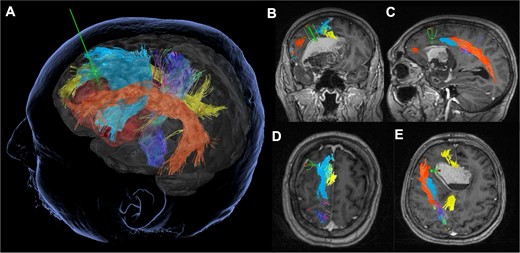

Preoperatively, a contrast-enhanced MRI with diffusion sequences for tractography dissection was performed. StealthStationS8© (Medtronic Inc., Louisville, CO, USA) was used for pre-surgical planning—tractography dissection, tumor modeling, and trajectory planning. The trajectory planning was utilized to maximize subcortical tract preservation, avoiding the bulk of the fronto-aslant tract (FAT), cingulate, uncinate fasciculus, and arcuate fasciculus. The inferior fronto-occipital fasciculus could not be dissected (Fig. 2).

Tubular retractor-assisted minimally invasive parafascicular surgery approach: Pre-operative tractography demonstrating the relationship of the left Sylvian fissure-centered dermoid to the corticospinal tract (dark blue), frontal-aslant tract (light blue), cingulate (yellow) and arcuate fasciculus (orange).